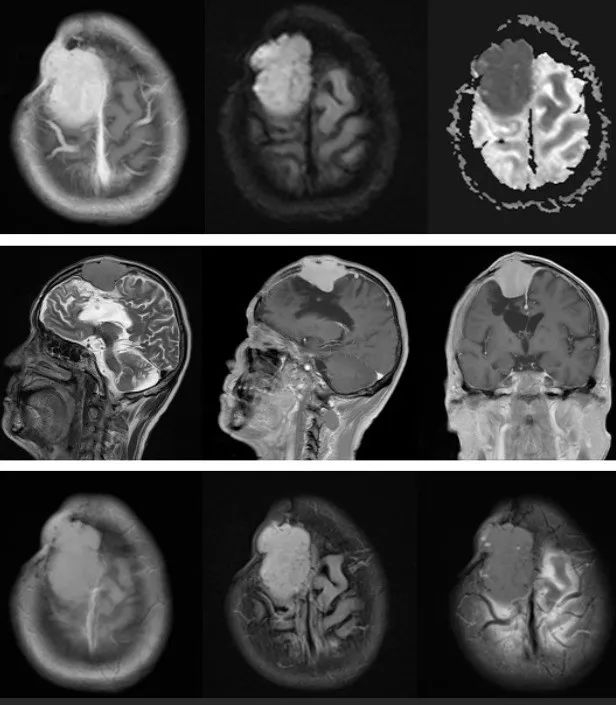

首刀、伽马刀后脑膜瘤多发恶化,INC巴教授Simpson 1级全切术,4年没有复发

一次手术只实施了部分切除。

二年病变复发,他接受了伽玛刀治疗,

三年病变竟然恶化成了多发性脑膜瘤。

较大脑膜瘤长在大静脉窦、大脑镰旁,INC巴教授手术全切,没有复发、无后遗症

2012年王女士体检时查出左侧额部大脑镰旁脑膜瘤,考虑肿瘤为良性,